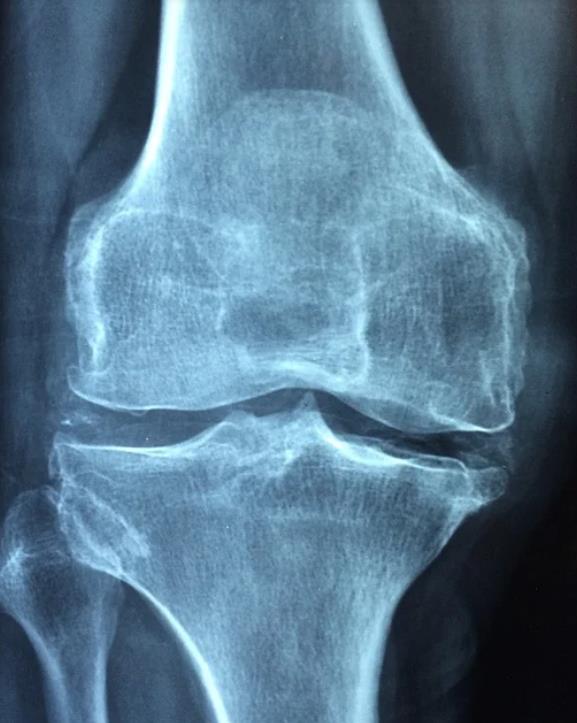

1. 퇴행성 관절염

병원을 찾는 환자들 중에 약 10~15%는 퇴행성관절염을 진단 받는다고 하는데요, 관절을 감싸고 있는 연골이 나이가 들어감에 따라 노화하거나 혹은 너무 많은 사용으로 손실이 생겨 발생하는 질환이라고 생각하면 됩니다.

평소 앉았다 일어날 때, 또 계단을 오를 때, 도보를 걸을 때 드드득, 혹은 드르륵 하면서 마치 뼈가 갈리는 듯한 소리가 난다면 퇴행성 관절염을 우선적으로 의심해봐야 합니다. 퇴행성 관절염에는 다리가 무겁게 느껴지거나, 무릎 아랫쪽 다리를 올리기 힘들다거나, 무릎 뒤쪽편이 당기는 증상도 있으니 참고하시면 좋을거 같습니다.

노화로 인해 생기는 경우가 많긴 하지만, 무릎쪽에 너무 무리를 줄 수 있는 과체중, 비만. 또 운동선수 같이 높은 강도의 훈련으로 인한 충격으로도 발생할 수 있기 때문에 꼭 나이 때문이라고 볼 수는 없습니다.